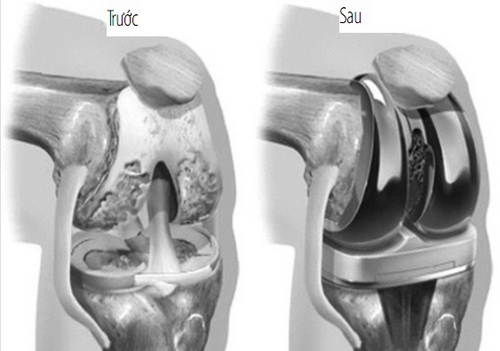

Tái tạo xương và sụn nhờ nano-biomaterials

Xương và sụn là những mô có khả năng phục hồi hạn chế, đặc biệt ở người lớn tuổi. Công nghệ nano đã mang đến hy vọng mới.

Vật liệu composite chứa hạt nano hydroxyapatite mô phỏng cấu trúc xương tự nhiên, giúp tăng độ bền và khả năng tái tạo.

Theo thống kê từ Journal of Orthopaedic Research, các ca cấy ghép sử dụng khung nano cho thấy tỷ lệ phục hồi

thành công cao hơn 30% so với phương pháp cấy ghép truyền thống. Điều này đặc biệt hữu ích trong điều trị gãy xương phức tạp,

bệnh loãng xương hoặc thoái hóa khớp.